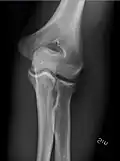

- Elbow - AP and Lateral. Radial head projections available on request

-

Lateral projection -

Anteroposterior projection -

Left elbow by 30 degrees internal oblique projection -

Left elbow by 30 degrees external oblique projection